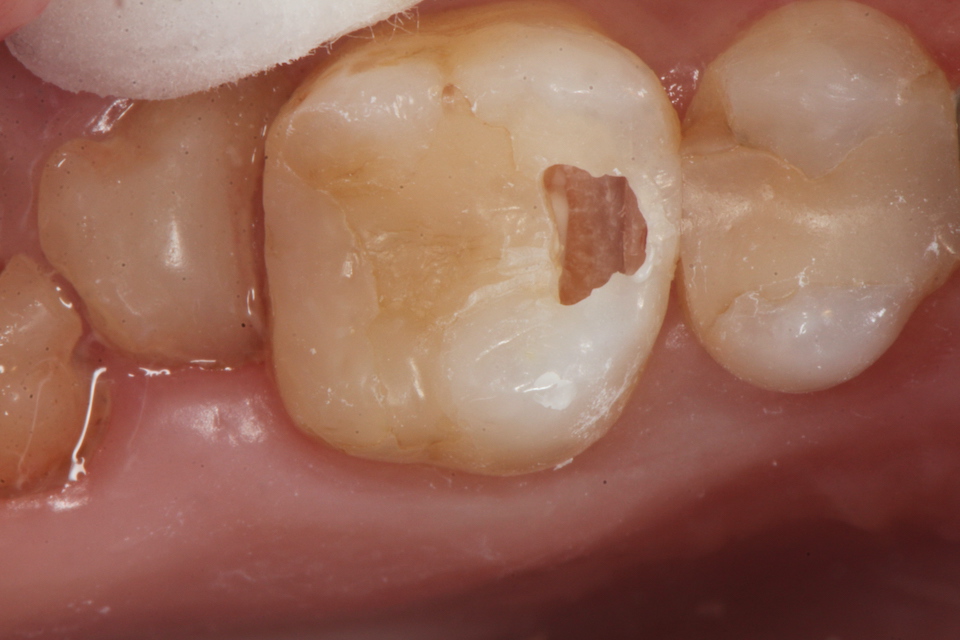

下顎7番の頬側歯茎部カリエスの原因 2025.06.04